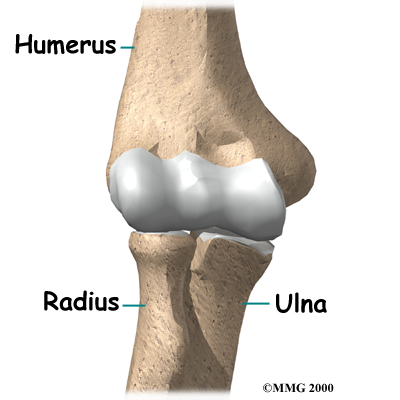

The elbow joint is made up of three bones: the humerus bone of the upper arm, and the ulna and radius bones of the forearm.

The elbow joint is made up of three bones: the humerus bone of the upper arm, and the ulna and radius bones of the forearm.

The ulna and the humerus meet at the elbow and form a hinge. This hinge allows the arm to straighten and bend. The large triceps muscle in the back of the arm attaches to the point on the end of the ulna (the olecranon). When the triceps muscle contracts, it straightens out the elbow. The biceps muscles in the front of the arm contract to bend the elbow.

The connection of the radius to the humerus and the ulna allows the forearm to rotate. The upper end of the radius is round. It turns against the ulna and the humerus as the forearm and hand turn from palm down (pronation) to palm up (supination).

In the elbow joint, the ends of the bones are covered with articular cartilage. Articular cartilage is a slick, smooth material. It protects the bone ends from friction when they rub together as the elbow moves. Articular cartilage is soft enough to act as a shock absorber. At the same time it is also tough enough to last a lifetime, if it is not injured.